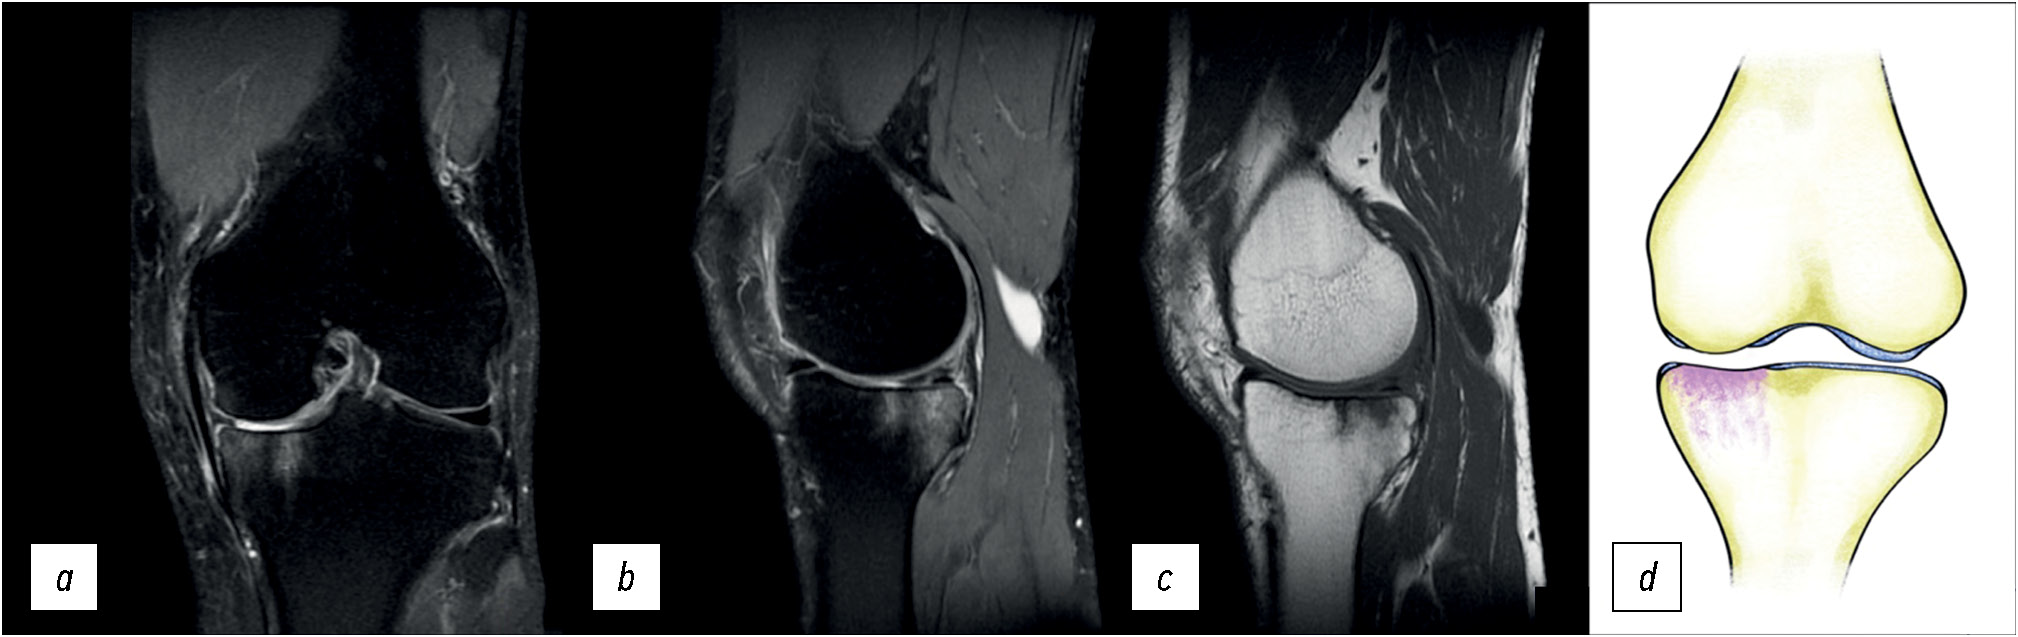

Пациент К., 72 года, обратился с жалобами на боль в области коленного сустава, которая появилась через сутки после длительной прогулки. На выполненных рентгенограммах патологии не выявлено. При МРТ-исследовании отмечен отёк области внутреннего мыщелка большеберцовой кости.

Особенности отёка костной ткани: в субхондральной зоне прослеживается искривлённая линия, которая является гипоинтенсивной на T1-взвешенных изображениях и в режиме PD с подавлением сигнала от жировой ткани и проходит параллельно суставной поверхности (рис. 2), что требует проведения дифференциальной диагностики с переломом в результате травмы [4].

Рис. 2. МР-томограммы коленного сустава: а, b — корональная и сагиттальная проекции в режиме PD FS с подавлением сигнала от жировой ткани, с — сагиттальная проекция в режиме T1, и графическое изображение (d) при субхондральном переломе внутреннего мыщелка большеберцовой кости. Стрелками отмечена линия перелома.

Fig. 2. MRI images of the knee. a — coronal view in PD FS mode with signal suppression from adipose tissue, b — sagittal view in S mode with signal suppression from adipose tissue, c — sagittal view in T1-weighted sequences and a graphic image (d) with a subchondral fracture of the medial condyle of the tibia. The arrows mark the fracture line.

Учитывая отсутствие в анамнезе травмы, данная патология была расценена [10] как субхондральный перелом на фоне недостаточной прочности (ослабления) кости. Возникает субхондральный перелом, как правило, у пациентов с остеопорозом на фоне выраженного снижения минеральной плотности костной ткани и после длительного пребывания на ногах. В зарубежной литературе обозначается аббревиатурой SIF/SIFK (Subchondral insufficiency fracture of the knee) [11].

Наличие линии в области отёка костной ткани позволяет провести дифференциальную диагностику между субхондральным переломом и начальной стадией асептического некроза, где подобной линии не прослеживается.